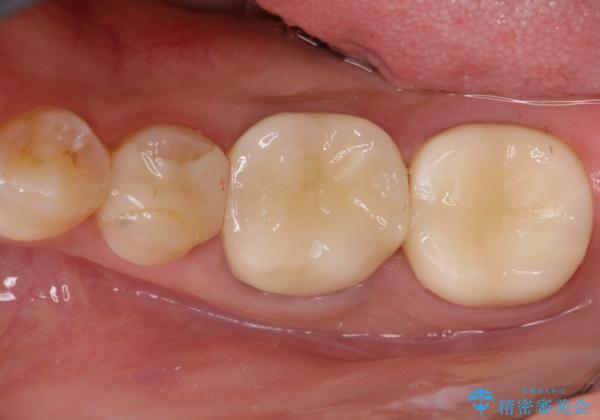

- 金属冠を白くしたいことを主訴に来院されました。

オールセラミッククラウン(st)にて修復しております。

根管治療も合わせて行なっているため、期間がかかっております。